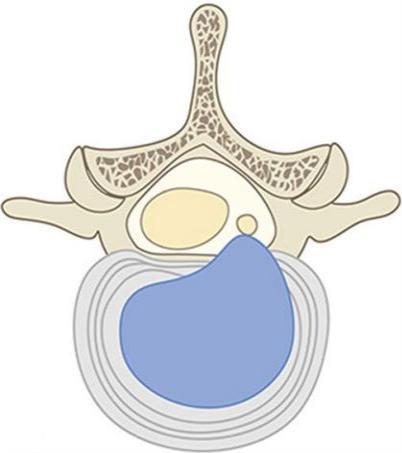

• 不同入路脊柱内镜手术治疗L4/5节段脱垂型腰椎间盘突出症的疗效比较

摘要:目的 观察经椎间孔入路内镜下腰椎间盘切除术(TELD)和经椎板间入路内镜下腰椎间盘摘除术(IELD)治疗L4/5节段脱垂型腰椎间盘突出症(LDH)的临床疗效。方法 回顾性分析2020年11月-2022年11月该院采用脊柱内镜手术治疗的75例L4/5节段脱垂型LDH患者的临床资料。根据手术入路的不同,将患者分为TELD组(53例)和IELD组(22例)。比较两组患者的手术情况和术后疗效。结果 与TELD组比较,IELD组的手术时间明显缩短,术中透视次数明显减少,差异均有统计学意义(P < 0.05);两组患者住院时间和并发症发生率比较,差异均无统计学意义(P > 0.05)。所有患者术后均获得12~19个月的随访。两组患者末次随访时的视觉模拟评分法(VAS)评分和Oswestry功能障碍指数(ODI)明显低于术前,且IELD组明显低于TELD组,差异均有统计学意义(P < 0.05)。按照突出物和神经根的不同位置进一步分析,两组肩上型患者(TELD组10例,IELD组6例)末次随访时的VAS评分和ODI明显低于术前,且IELD组末次随访时的VAS评分明显低于TELD组,差异均有统计学意义(P < 0.05);两组腋下型患者(TELD组8例,IELD组16例)末次随访时的VAS评分和ODI明显低于术前,且IELD组明显低于TELD组,差异均有统计学意义(P < 0.05);35例肩前型患者经TELD术后,末次随访时的VAS评分和ODI明显低于术前,差异有统计学意义(P < 0.05)。按照突出物的不同Lee分区进一步分析,两组Lee Ⅲ区患者(TELD组44例,IELD组10例)末次随访时的VAS评分和ODI明显低于术前,且IELD组的ODI明显低于TELD组,差异均有统计学意义(P < 0.05);两组Lee Ⅳ区患者(TELD组9例,IELD组12例)末次随访时的VAS评分和ODI明显低于术前,且IELD组明显低于TELD组,差异均有统计学意义(P < 0.05)。结论 采用TELD和IELD治疗L4/5节段脱垂型LDH,均可获得较满意的减压效果,但IELD的手术时间相对较短,X线透视次数较少,且对肩上型、腋下型、Lee Ⅲ区和Lee Ⅳ区的减压效果更有优势。